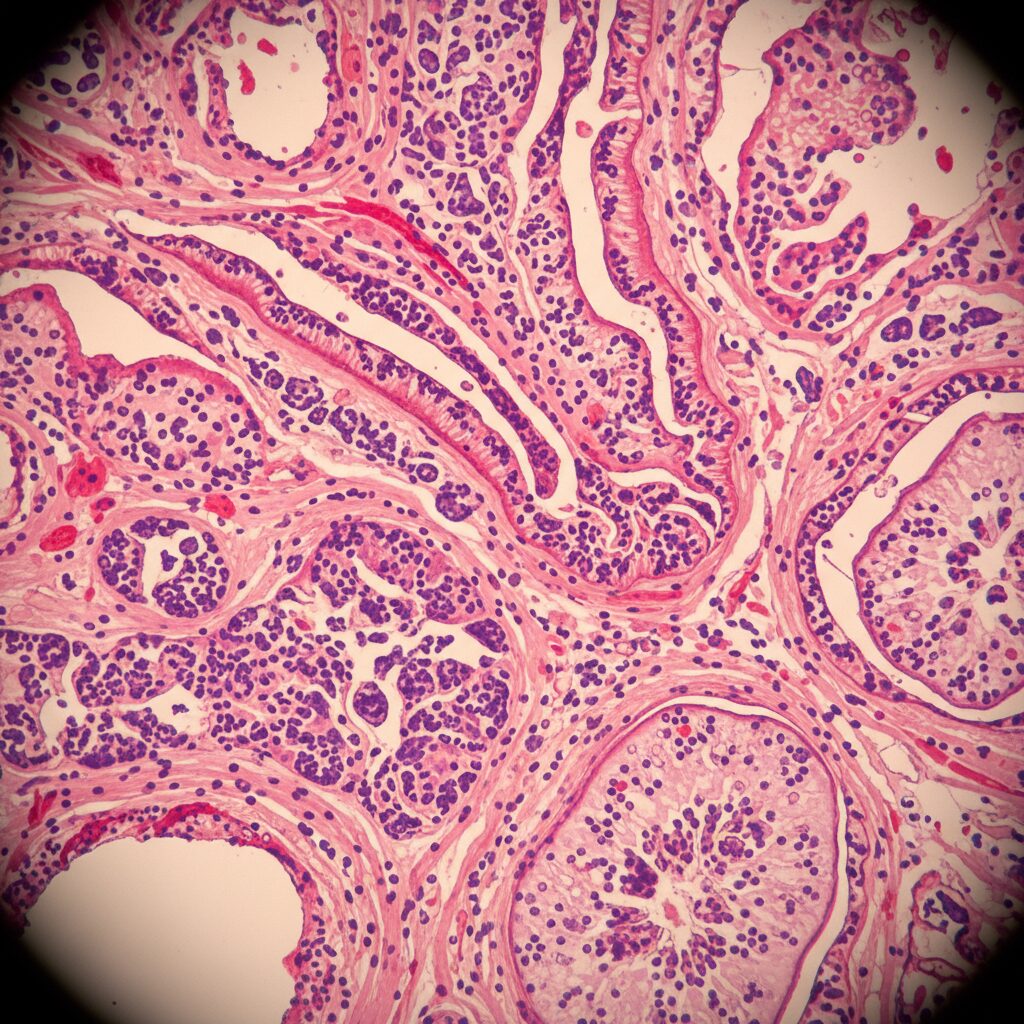

Animal models provide encouraging data.

In lipopolysaccharide-induced Acute Lung Injury models, BDP-12 treatment resulted in:

• Reduced alveolar wall thickening

• Lower pulmonary edema

• Decreased protein leakage

• Reduced immune cell infiltration

• Lower cytokine levels in bronchoalveolar lavage fluid

In sepsis-induced Acute Lung Injury models, survival improved significantly.

These findings suggest meaningful biological activity. However, it is important to remember that results in mice do not guarantee success in humans.